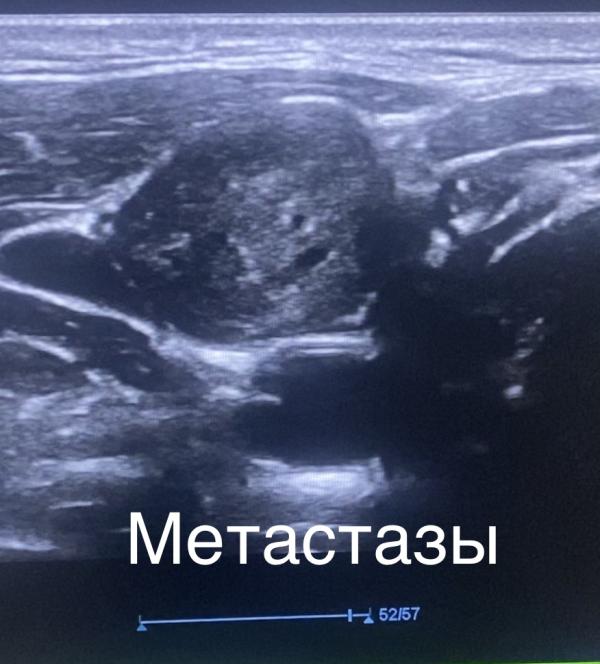

Итак ставлю датчик на шею и впадаю в шок.

Сразу мысли в голове: это не просто увеличенные лимфоузлы из-за инфекции… что -то тут не так. Надо найти очаг! Посмотри щитовидку!

И вот перехожу на осмотр щитовидки и вижу образование (по всем характеристикам похоже на рак) и тут все пазлы сошлись…

У девочки оказался рак щитовидной железы, а эти шишки были метастазы в лимфоузлах шеи😭

Сначала появляется первичный очаг - это рак щитовидки и от него пошли метастазы в лимфоузлы ближайшие( это шея)